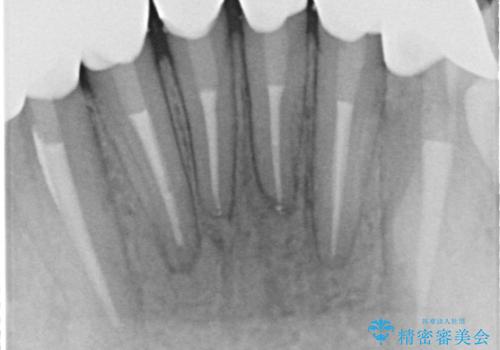

【オールセラミック】下の前歯が痛い。

- 以前に治療した前歯が痛むことを主訴に来院されました。

根っこに病気があり、根管治療から被せ物まで治療を行いました。

根管治療を行った後、3ヶ月間治癒の確認をしてからオールセラミックスペシャルで治療を行いました。